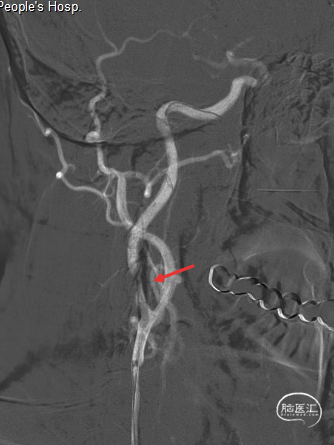

撤出保护伞观察10分钟复查造影,无弹性回缩,狭窄明显好转,血流明显改善(箭头处),结束手术。